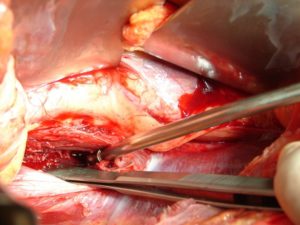

Στη δεύτερη φάση που πραγματοποιήθηκε μετά από δύο ημέρες, κατόπιν προσθίας δεξιάς και αριστεράς οπισθιο-περιτοναϊκής προσπέλασης στη κοιλιακή χώρα, εγένετο παροχέτευση των προ-παρασπονδυλικών αποστημάτων. Δόθηκε υλικό από τους ιστούς και την πυώδη συλλογή για καλλιέργεια.

Εικόνα 5 (α,β)

- α

- β